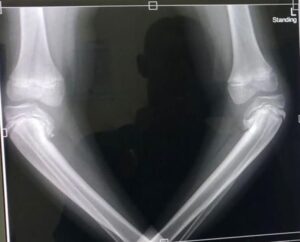

Voorbeelden van de misvormingen bij de jongeren getroffen door malaria en vitamine D tekort.